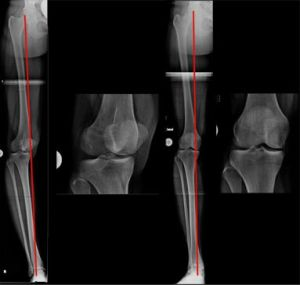

Die Linie, die Hüftkopfmitte und Sprunggelenksmitte verbindet, ist die mechanische Achse (MA) eines Beines (Bild 1a). Durch die MA wird das Knie in ein inneres (medialen) und äußeres (medialen) Kompartiment geteilt.

Sie verläuft im Normalfall durch die Mitte (Zentrum) des Kniegelenkes und führt dort zu einer Lastverteilung, die zu 75% die Innenseite und zu 25% die Außeneite des Gelenkes trifft.

Dies ist die „normale“ Lastverteilung zwischen dem inneren und äußeren Kompartiment des Knies.